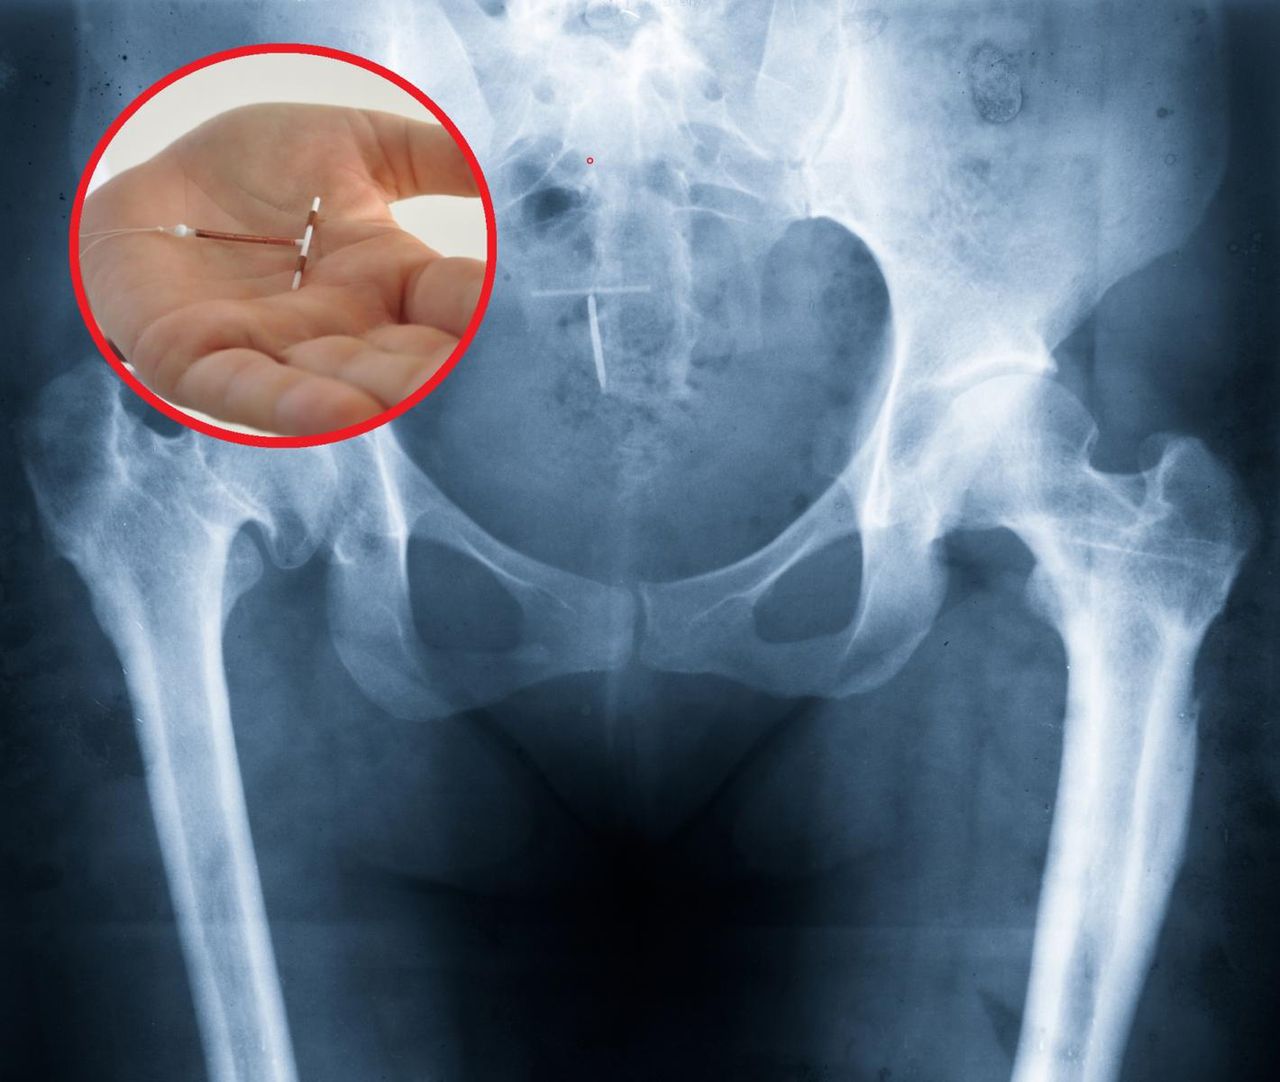

To niewielkie urządzenie w kształcie litery T jest umieszczane w macicy przez lekarza lub pielęgniarkę. Gdy znajduje się w macicy, uwalnia miedź, która utrudnia plemnikom przeżycie i dotarcie do komórki jajowej, zapobiega także powstaniu zarodka poprzez uniemożliwienie połączenia plemnika z komórką jajową. Spirala antykoncepcyjna może chronić przed zajściem w ciążę od 5 do nawet 10 lat.

Wkładka ta powinna być usuwana jedynie przez przeszkolonego lekarza lub pielęgniarkę.